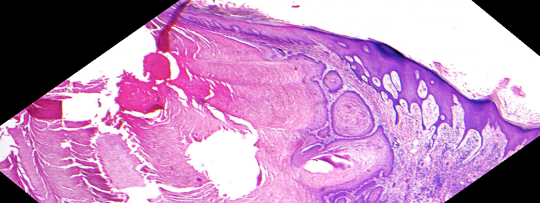

VA9: Left Forearm, Squamous Cell Carcinoma, Invasive